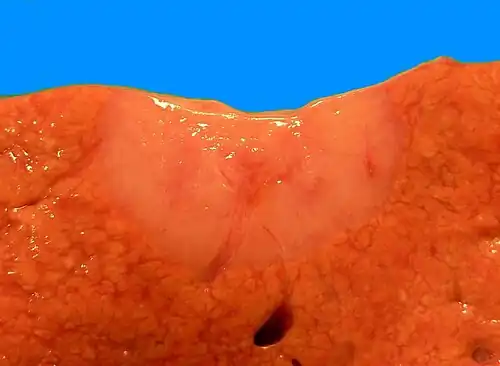

Gross pathologic appearance of a large bile duct hamartoma.

Gross pathologic appearance of a large bile duct hamartoma.